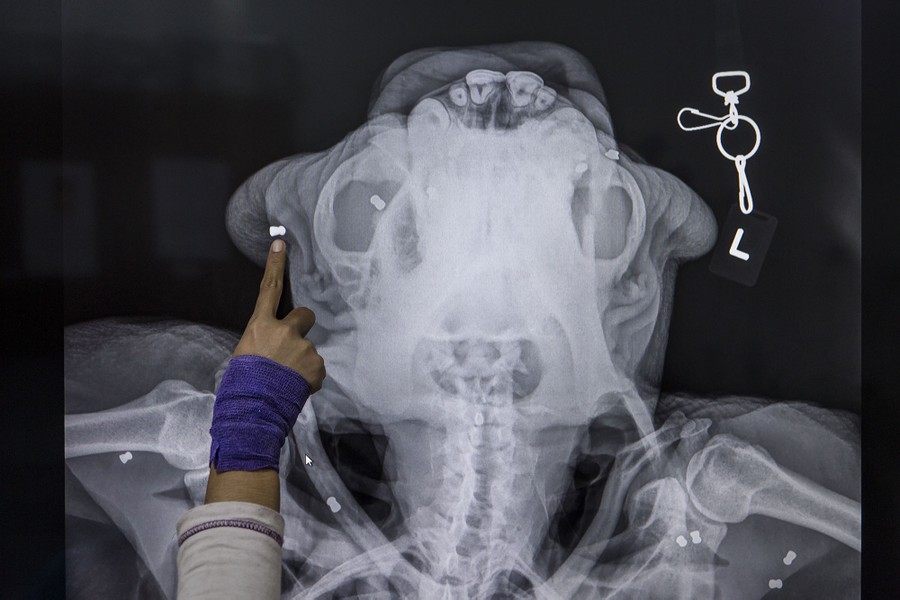

Read moreA veterinary staff member shows an x-ray photo of Tengku, a Sumatran orangutan (Pongo abelii) who was rescued from the community farm nearly two weeks ago, and was found to have more than 60 air rifle pellets embedded in his body. Photographed inside a quarantine facility at the Sumatran Orangutan Conservation Program's rehabilitation center on November 10, 2016 in Kuta Mbelin, Indonesia. Orangutans in Indonesia have been known to be on the verge of extinction as a result of deforestation and poaching. Found mostly in South-East Asia, where they live on the islands of Sumatra and Borneo, the endangered species continue to lose their habitat as a result of corporate expansion in a developing economy. Indonesia approved palm oil concessions on nearly 15 million acres of peatlands over the past years and thousands of square miles have been cleared for plantations, including the lowland areas that are the prime habitat for orangutans. #

Ulet Ifansasti / Getty -